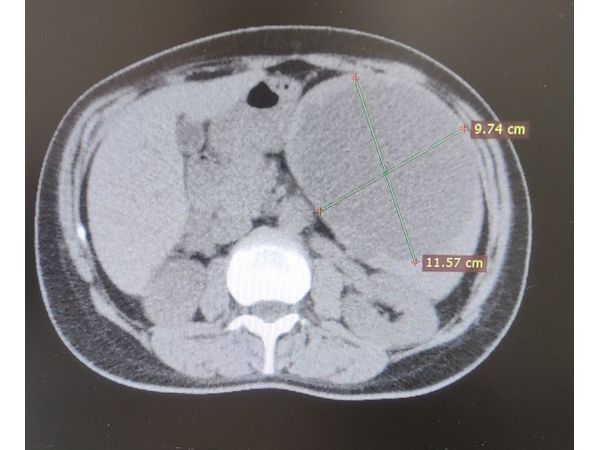

Рентген селезенки